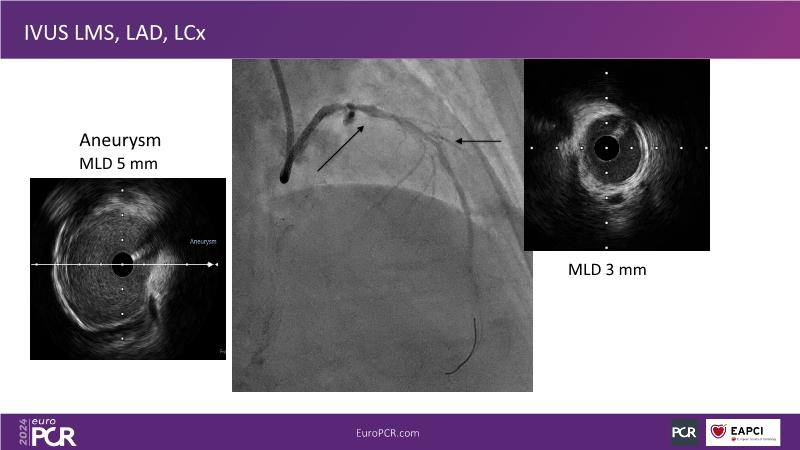

From innovation to reality: the impact of Cre8 EVO technology on complex PCI

Sponsored by Alvimedica